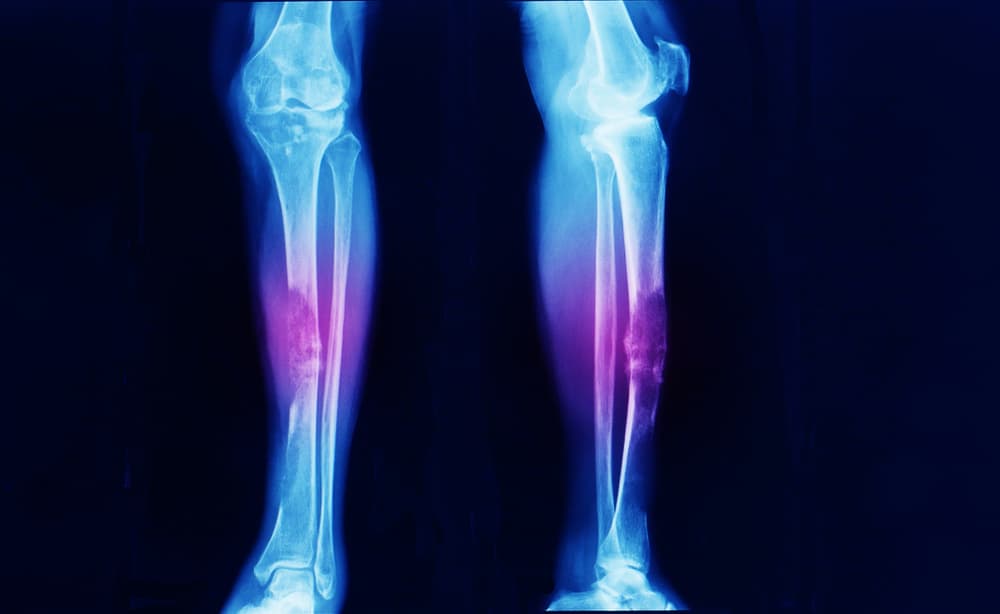

Before treating bone cancer, doctors will try to know the extent of the cancer. This is usually done through an x-ray, as this allows doctors to see the damage the cancer has done to the bone.